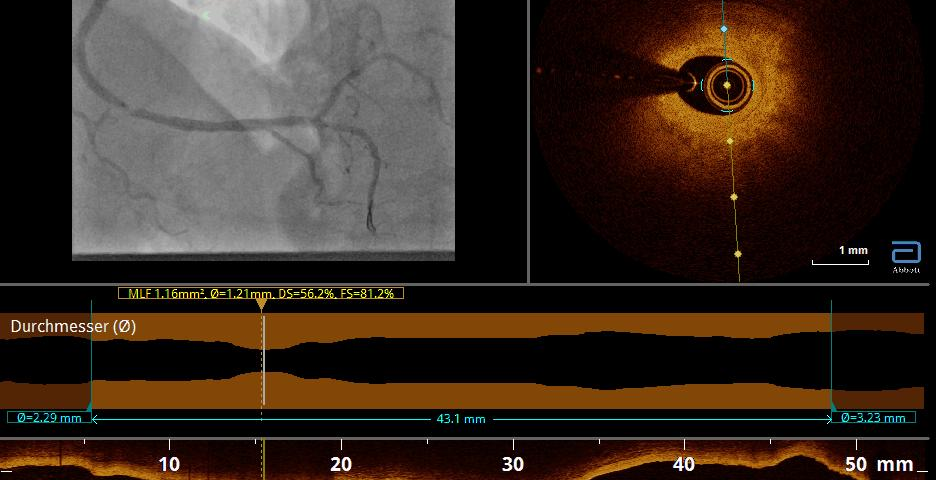

SIEGEN. Bei einer Herzkatheteruntersuchung kann das Herz von innen heraus untersucht werden. Alle Herzkammern sowie angrenzende Gefäße sind auf diese Weise zugänglich. Das bietet viele Vorteile, vor allem aber die Option, bei Bedarf gleichzeitig zu behandeln. Die Intervention gilt als risikoarm und liefert dank moderner Medizintechnik aussagekräftige diagnostische Ergebnisse.

Was genau ist ein Herzkatheter? Dabei handelt es sich um einen flexiblen, dünnen Schlauch, der an seiner Spitze verschiedene Instrumente tragen kann. Damit kann die Untersuchung des Herzens erfolgen. Dieser Katheter wird am Arm oder in der Leiste in ein größeres Blutgefäß eingeführt und dann unter Röntgenkontrolle bis in das Herz vorgeschoben. Dazu muss lediglich die Zugangsstelle örtlich betäubt werden. Das Vorschieben des Katheters spüren Patienten hingegen nicht.

„Die Kammern des linken Herzens erreichen wir über das arterielle Blutgefäßsystem. Die Untersuchung wird oft kurz als Linksherzkatheter bezeichnet. Sie dient vorrangig der Diagnostik und Therapie der Herzkranzarterien, die direkt am Herzen von der Hauptschlagader abgehen. Eine Linksherzkatheteruntersuchung führen wir in erster Linie bei einer koronaren Herzerkrankung sowie im Notfall bei einem Herzinfarkt durch“, erklärt Prof. Dr. Dursun Gündüz, Chefarzt der Kardiologie.

Herzkatheteruntersuchungen erlauben neben der Diagnostik auch therapeutische Interventionen, zum Beispiel an den Herzklappen, den Herzkranzgefäßen oder den Herzwänden. Dank des schonenden, minimalinvasiven Verfahrens kann in vielen Fällen auf offene Operationen am Herzen verzichtet werden.